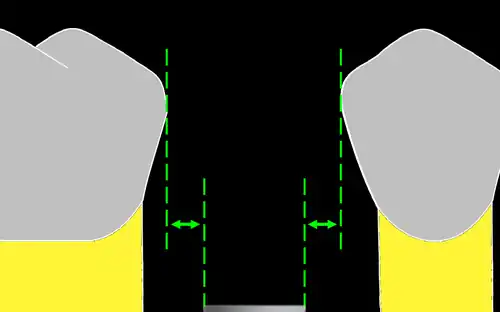

In implant dentistry, running room refers to the apico-coronal distance between the platform of a dental implant and the gingival margin. It is a critical factor in restorative implant dentistry because it is effectively the "vertical distance [available subgingivaly] to make a transition from the smaller diameter prosthetic platform of an implant to the larger cross-sectional cervical shape of the tooth being restored."[1] The term was coined by Jonathan Zamzok, a Manhattan prosthodontist, in the late 1990s.[2]

Adequate running room is necessary to allow the implant-supported crown to exhibit a tooth-shaped contour despite the smaller diameter and circular nature of implant platforms.[3] For example, the mean mesial-distal dimension of a maxillary central incisor at the points at which it contacts the adjacent teeth is 8.6 mm, and the mean mesial-distal dimension of the same tooth at the cementoenamel junction (CEJ) is 6.4 mm.[4] Even though the implant diameter chosen for the maxillary central incisor is usually around 4–5 mm, the supragingival tooth contours need to mimic those of the natural tooth if esthetic success is intended.

As the anatomical crown and root tapers towards the apex, the mesial-distal dimension decreases, and so the mean mesial-distal dimension at the marginal crest of bone, which lies approximately 2 mm apical to the CEJ, is smaller. The tooth has the apico-coronal distance from the marginal crest of bone to the contact point in order to increase from the much narrower mesial-distal dimension to the greater mesial-distal dimension, and this distance is subgingival (below the gum line). Running room refers to this subgingival apico-coronal distance.

When implants are placed too palatally or lingually due to aberrant anatomical landmarks, bone resorption or surgical error, it is wise to place the implant more apically to increase the available running room in order to allow for a more convex emergence profile and avoid a buccal ridge-lap of the prosthetic crown in fixed partial denture cases.[5] Similarly, when narrower than normal implant connections are used, deeper placement may enhance one's ability to generate an optimal emergence profile.